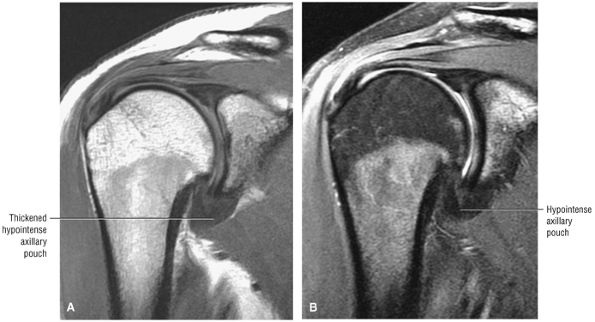

pouch that attaches to the inferior two thirds of the entire circumference of the glenoid by means of the labrum (Figs. 8.80 and 8.81).37,62 The IGHL is lax in adduction and taut in abduction and external rotation (Fig. 8.82). As it tightens with increasing abduction, the anterior and posterior bands move superiorly with respect to the humeral head. At 90° of abduction, the IGHL is the primary restraint for anterior and posterior dislocations.63 The axillary pouch is located between the anterior and posterior bands and, like the anterior and posterior bands, is lax with the arm by the patient—s side in the adducted position. The axillary pouch extends inferior to the body of the glenohumeral joint as a redundancy of thickened capsular tissue best visualized on coronal oblique images.

The inferior glenoid labrum and axillary pouch are clearly demonstrated on these oblique images. Subscapularis bursal fluid may extend inferior and medial to the inferior glenoid on anterior coronal images.

On midcoronal images, the muscle belly of the supraspinatus extends laterally beyond the glenoid before its central tendon reaches the musculotendinous junction of the rotator cuff. The axillary pouch of the IGHL, with its attachment to the anatomic neck of the humerus and the inferior pole of the glenoid, can also be seen on these images. It is not unusual to see variable

amounts of fluid in the axillary pouch in the presence of a joint effusion. Otherwise, the axillary pouch is collapsed. The presence of a glenohumeral joint effusion is associated with osteoarthritis and rotator cuff disease.42 The axillary pouch can be followed from anterior to posterior on coronal oblique images through the shoulder. -